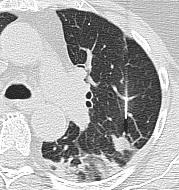

Female 73 Y Lung metastasis from uterine sarcoma

错误?

穿刺针道长,导致出血和肺不张(atelectasis)